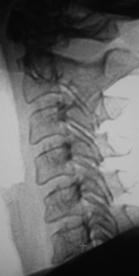

Иллюстрации 1, 2, 3. Определяется «выпрямленность» шейного лордоза, неравномерное сужение межпозвонковых щелей в сегментах С2-С3, С3-С4. Резкое сужение межпозвонковых щелей в сегментах С4-С5, С5-С6, С6-С7, с выраженным субхондральным склерозом тел позвонков, неровностью замыкательных пластинок, образованием остроконечных остеофитов по передней поверхности тел позвонков. В дугоотросчатых суставах определяется сужение суставных щелей с выраженным субхондральным склерозом. На иллюстрации 2 хорошо дифференцируется остеосклеротическая перестройка тел С4, С5, С6, С7, как компенсаторная приспособительная реакция, в результате анатомической и функциональной несостоятельности межпозвонковых дисков.